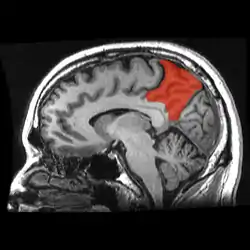

![]() Sagittal MRI slice with the precuneus shown in red. | |